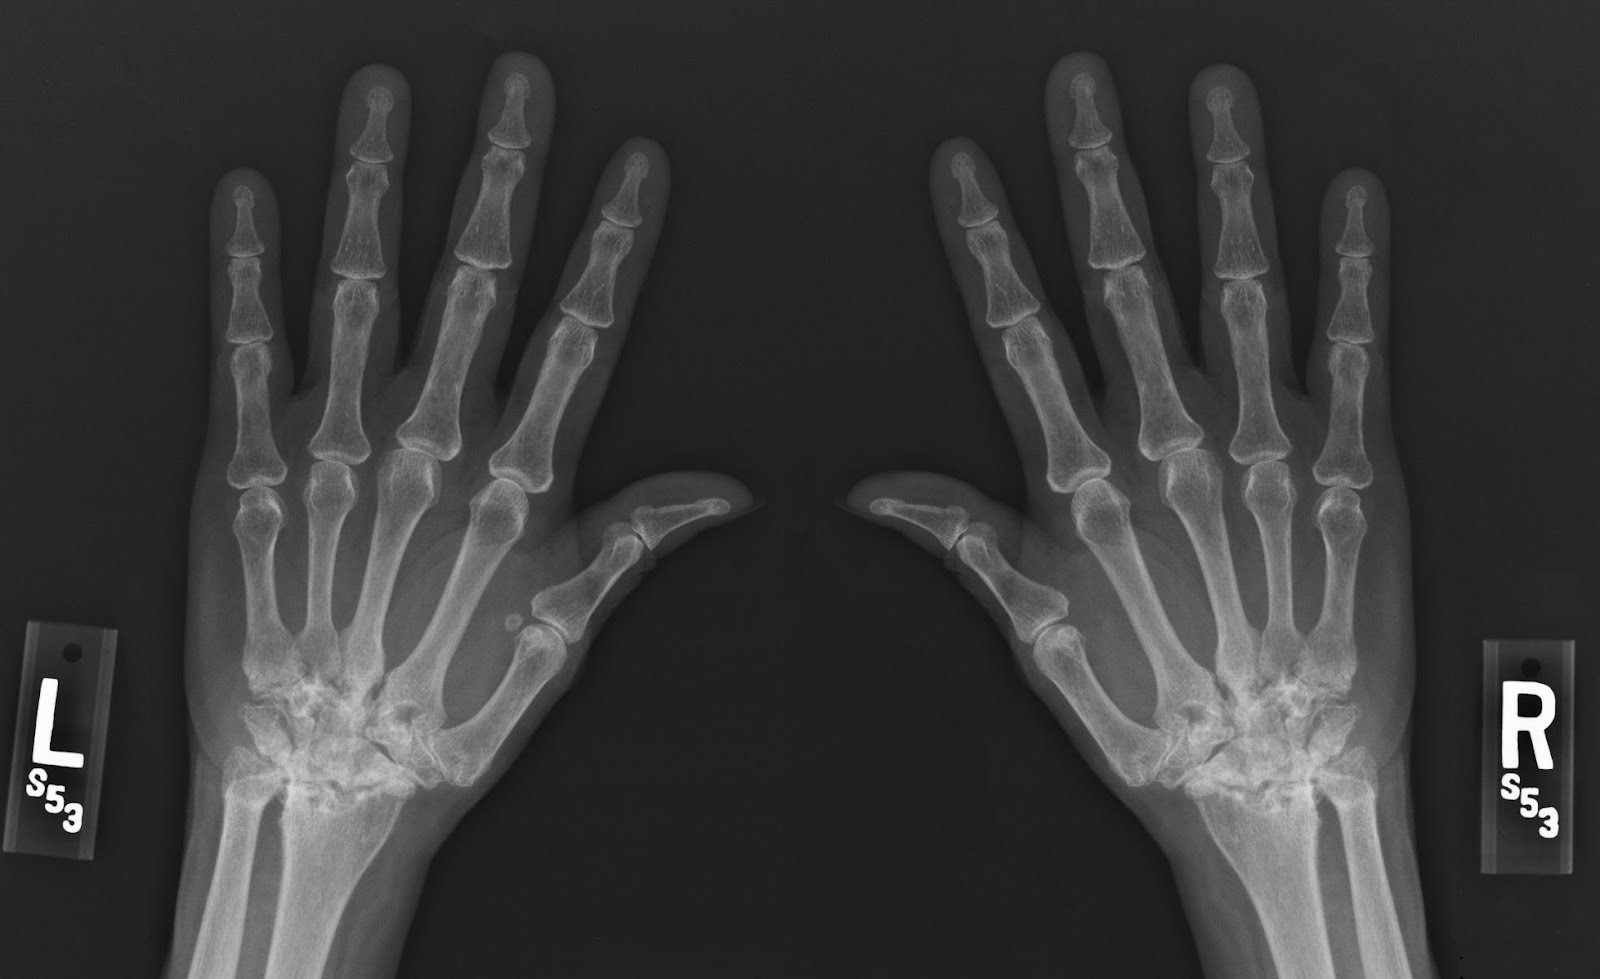

Question 2

A 37-year-old woman comes to the physician because of progressive pain and stiffness in her hands and wrists for the past 1 year. Her hands are stiff in the morning; the stiffness improves as she starts her chores. Physical examination shows bilateral swelling and tenderness of the wrists and metacarpophalangeal joints. Her range of motion is limited by pain. Laboratory studies show an increased erythrocyte sedimentation rate. This patient's condition is most likely associated with which of the following findings?